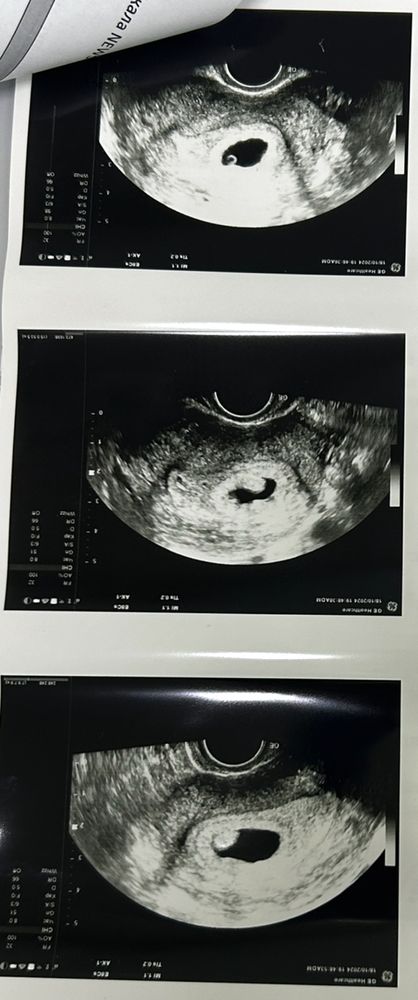

Девочки, привет! Может, кто умеет расшифровывать снимки, или у кого было похожее. Была вчера на узи, 25 дпо, 13 день задержки. Ставят анэмбрионию+какая то непонятная гиперэхогенная структура. Она меня больше всего испугала. СВД плодного яйца вырос с 8,4 до 22мм за 4 дня, появился желточный мешочек, ранее его не было. Что это вообще может быть? Помогите, пожалуйста, умоляю, все глаза выплакала. Про позднюю овуляцию никто даже слышать не хочет, уже хотели положить на сохранение (как я поняла, с дальнейшей чисткой). Хгч сдавала, растет за 3 дня в 4 раза, но насколько я знаю, при анэмбрионии это не показатель.